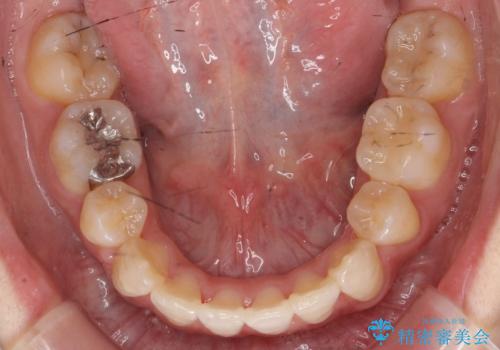

八重歯の治療 仕上がり重視で

- 八重歯を主訴に来院。

仕上がり重視とのことで、小臼歯を抜歯し、スタンダードな治療方法で仕上げています。

上下の小臼歯を抜歯しています。

矯正用インプラントアンカーを使用してしっかり前歯を下げたため、口元が大きく改善しています。